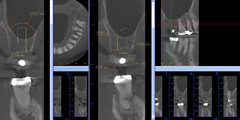

下顎の解剖学的リスク

下歯槽管までの距離の把握。クロスセクショナル像における下顎骨体の形態の把握。下顎骨体の血管と神経の走行、骨の幅、骨質、骨量等を把握。インプラント手術のリスクを判断する事が可能。